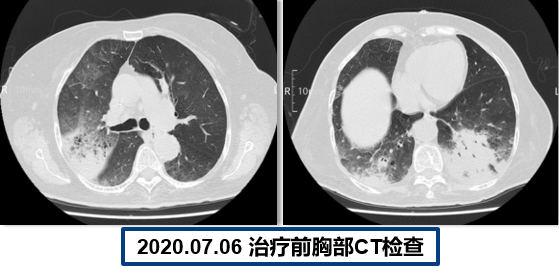

为提升肺癌前线免疫联合抗血管治疗的诊疗观念,学习与追踪肺癌领域诊疗最前沿知识,充分交流免疫/抗血管用药不良反应管理临床经验,【An例说】肺癌病例项目,征集大量临床高质量免疫联合抗血管治疗肺癌病例,并邀请全国各区域中青年及高职称医生与顶级TOP KOL互动发声!通过理念结合实践,研究结合病例,线上联动,共同促进学术由KOL/ROL向中青年医生下沉,为提升我国肺癌诊疗整体水平势在必行。免疫治疗的出现,对于晚期肺癌患者而言,显著提高了患者的生存质量及延长生存期,多项研究表明免疫治疗对于PD-L1表达阴性的患者也具有一定的治疗效果。为此,上海长海医院(海军军医大学第一附属医院)团队为您带来一例肺癌免疫联合抗血管病例分享。 患者,女性,78岁 2017年体检时发现左下肺结节,未行诊断及治疗。 2018.11.21、2019.09.24胸部CT均提示病灶较前变大,仍未诊治。 影像学检查 2020.01初逐渐出现胸闷、气短,活动后尤为明显。多次就诊于当地医院输液治疗(具体不详)。入院前2周胸闷,气急症状加重,无发热,无明显咳嗽,咳痰。2020.06.23入院。 影像学检查 既往史:高血压病30余年,最高血压170/90mmHg,规律服用美托洛尔12.5mg+利血平 0.1mg/日,自诉血压控制可。 个人史:无特殊 婚育史:无特殊 家族史:无特殊 T:37.0℃ P:104次/分 R:30次/分 BP:134/58mmHg 右肺及左肺可闻及湿罗音,左下肺呼吸音弱,无胸膜摩擦音。 心脏查体无异常。 入院后 CT引导下肺穿刺 穿刺后无咳嗽咯血,胸闷气急症状无加重。 6.25 出院等病理。 自行口服易瑞沙治疗,家中持续吸氧。 出院后3天突发病情变化: 6.28 凌晨1点左右,如厕后出现呼吸困难加重,晕倒。家属约2点发现,送至急诊,急诊予化痰、平喘、抗感染等对症治疗。 影像学检查 急诊检验检查: 【血气分析】PH 7.35、PO2 45.9mmHg、PCO2 62.6mmHg 【BNP】23.38pg/ml;【D-二聚体】0.32 【血常规】WBC:9.23×109/L、RBC:3.58×1012/L、HGB:98g/L、N%:80.2%、PLT:203×109/L。 【炎症指标】CRP:2.95mg/L;ESR:4mm/H;PCT:0.045ng/ml 【心电图】1. 窦性心动过速、2. ST-T异常。 血气分析 2020.06.29再次入院:左下肺腺癌、Ⅱ型呼吸衰竭、右肺阴影待查。 右肺渗出原因分析:感染?肿瘤进展?药物相关? 血常规变化: 选择治疗方案: 1. 两肺炎症,纵隔稍大淋巴结,炎症较2020.6.24进展,建议抗炎治疗后复查; 2. 左侧胸腔少许积液; 3. 两肺肺气肿、肺大泡,右肺中叶钙化灶; 4. 右侧第4肋骨皮质扭曲,请结合临床; 5. 甲状腺两侧结节,请结合超声。 右下肺腺癌 PD-L1无表达 抗血管生成与免疫联合的优点: 1、抗血管生成,靶点全面、强效抑制 2、抑制肿瘤细胞增殖和迁移,重塑肿瘤微环境,联合增效 3、肿瘤血管正常化及重塑,减轻免疫抑制状态 4、增加免疫效应细胞浸润 5、免疫刺激作用,激活免疫效应细胞 信迪利单抗联合安罗替尼的临床研究:这是一项前瞻性、非随机、三臂、Ib期临床研究。 临床研究试验设计 临床研究PFS和OS曲线 安罗替尼联合信迪利单抗一线治疗NSCLC,ORR达72.7%,DCR达100%,mPFS=15.6m,24m,OS率83.9%,表现出良好的治疗潜力。 派安普利单抗联合安罗替尼的临床研究:随机、双盲、多中心III期临床研究(NCT03866980) 临床研究试验设计 安尼可联合安罗疗效的ORR和DCR分析 数据截止日期:2021.1.13,共26例患者入组安尼可联合安罗替尼组,21例患者至少完成一次疗效评价。 帕博利珠单抗+安罗替尼 8mg。 治疗过程影像学检查 疗效评估: 2021.08.03: 疗效评估PR,截止目前PFS=15m。 该病例采用PD-L1抑制剂帕博利珠单抗联合小分子多靶点抗血管生成药物安罗替尼治疗老年肺腺癌患者,获得了15个月的PFS,提示对于驱动基因阴性,PD-L1无表达的晚期非小细胞肺癌患者免疫联合抗血管生成药物治疗是NSCLC患者一线治疗的选择和手段之一。 Impower150研究显示,贝伐珠单抗联合PD-L1抑制剂阿替利珠单抗+化疗显著改善了无突变非鳞NSCLC患者的PFS,中位OS达19.4个月(对照组14.7个月),ORR为71%。但治疗相关的毒副反应较大,一定程度上影响患者生活质量。小分子TKI联合免疫作为肿瘤去化疗联合治疗模式,越来越受到关注,前期探索性前瞻性随机临床研究包括信迪利单抗+安罗替尼(ACTION研究)、派安普利单抗+安罗替尼(AK105-301研究)和卡瑞利珠单抗+Apatinib/ target=_blank class=infotextkey>阿帕替尼(SHR-1210-III-315 研究)等一线治疗驱动基因阴性晚期NSCLC均得到了较好结果, 信迪利单抗联合安罗替尼组ORR达72%,DCR100%,中位PFS15.6个月,2年OS率83.9%,耐受性良好,显示出多靶点抗血管生成药物联合的良好应用前景。 免疫与抗血管生成药物以及与其他药物或方式联合该如何排兵布阵,肺癌治疗如何真正践行个体化和精准化,还有许多问题和挑战,有待进一步研究拓展和证实。 病例分享 焦洋 教授 上海长海医院,副主任医师,副教授 海军军医大学长海医院呼吸与危重症医学科 美国田纳西州大学附属医院呼吸与危重症医学科访问学者 上海市医学会呼吸分会感染学组秘书 中国老年医学会感染诊治与合理用药学术委员会委员 专业方向:疑难、复杂肺部感染及呼吸危重症的救治,肺癌的早期诊断和治疗。 专家点评 韩一平 教授 海军军医大学第一附属医院 呼吸与危重症医学科教授、主任医师 博士生导师 海军军医大学第一附属医院临床教育中心主任 中华医学会呼吸分会肺癌学组委员 中国医药教育协会肺部肿瘤专委会常委 中国医师协会全科分会委员,上海全科分会副会长 《中国肿瘤生物治疗杂志》《中国全科医学杂志》 《第二军医大学学报》《内科年鉴》等编委 获校“特级优秀教师”,上海市“育才奖” 首届上海“最美女医生” 主编发表教材或专著5部,近年发表文论50余篇 *仅供医学药学专业人士阅读 文章来源:ONCO前沿案例详情